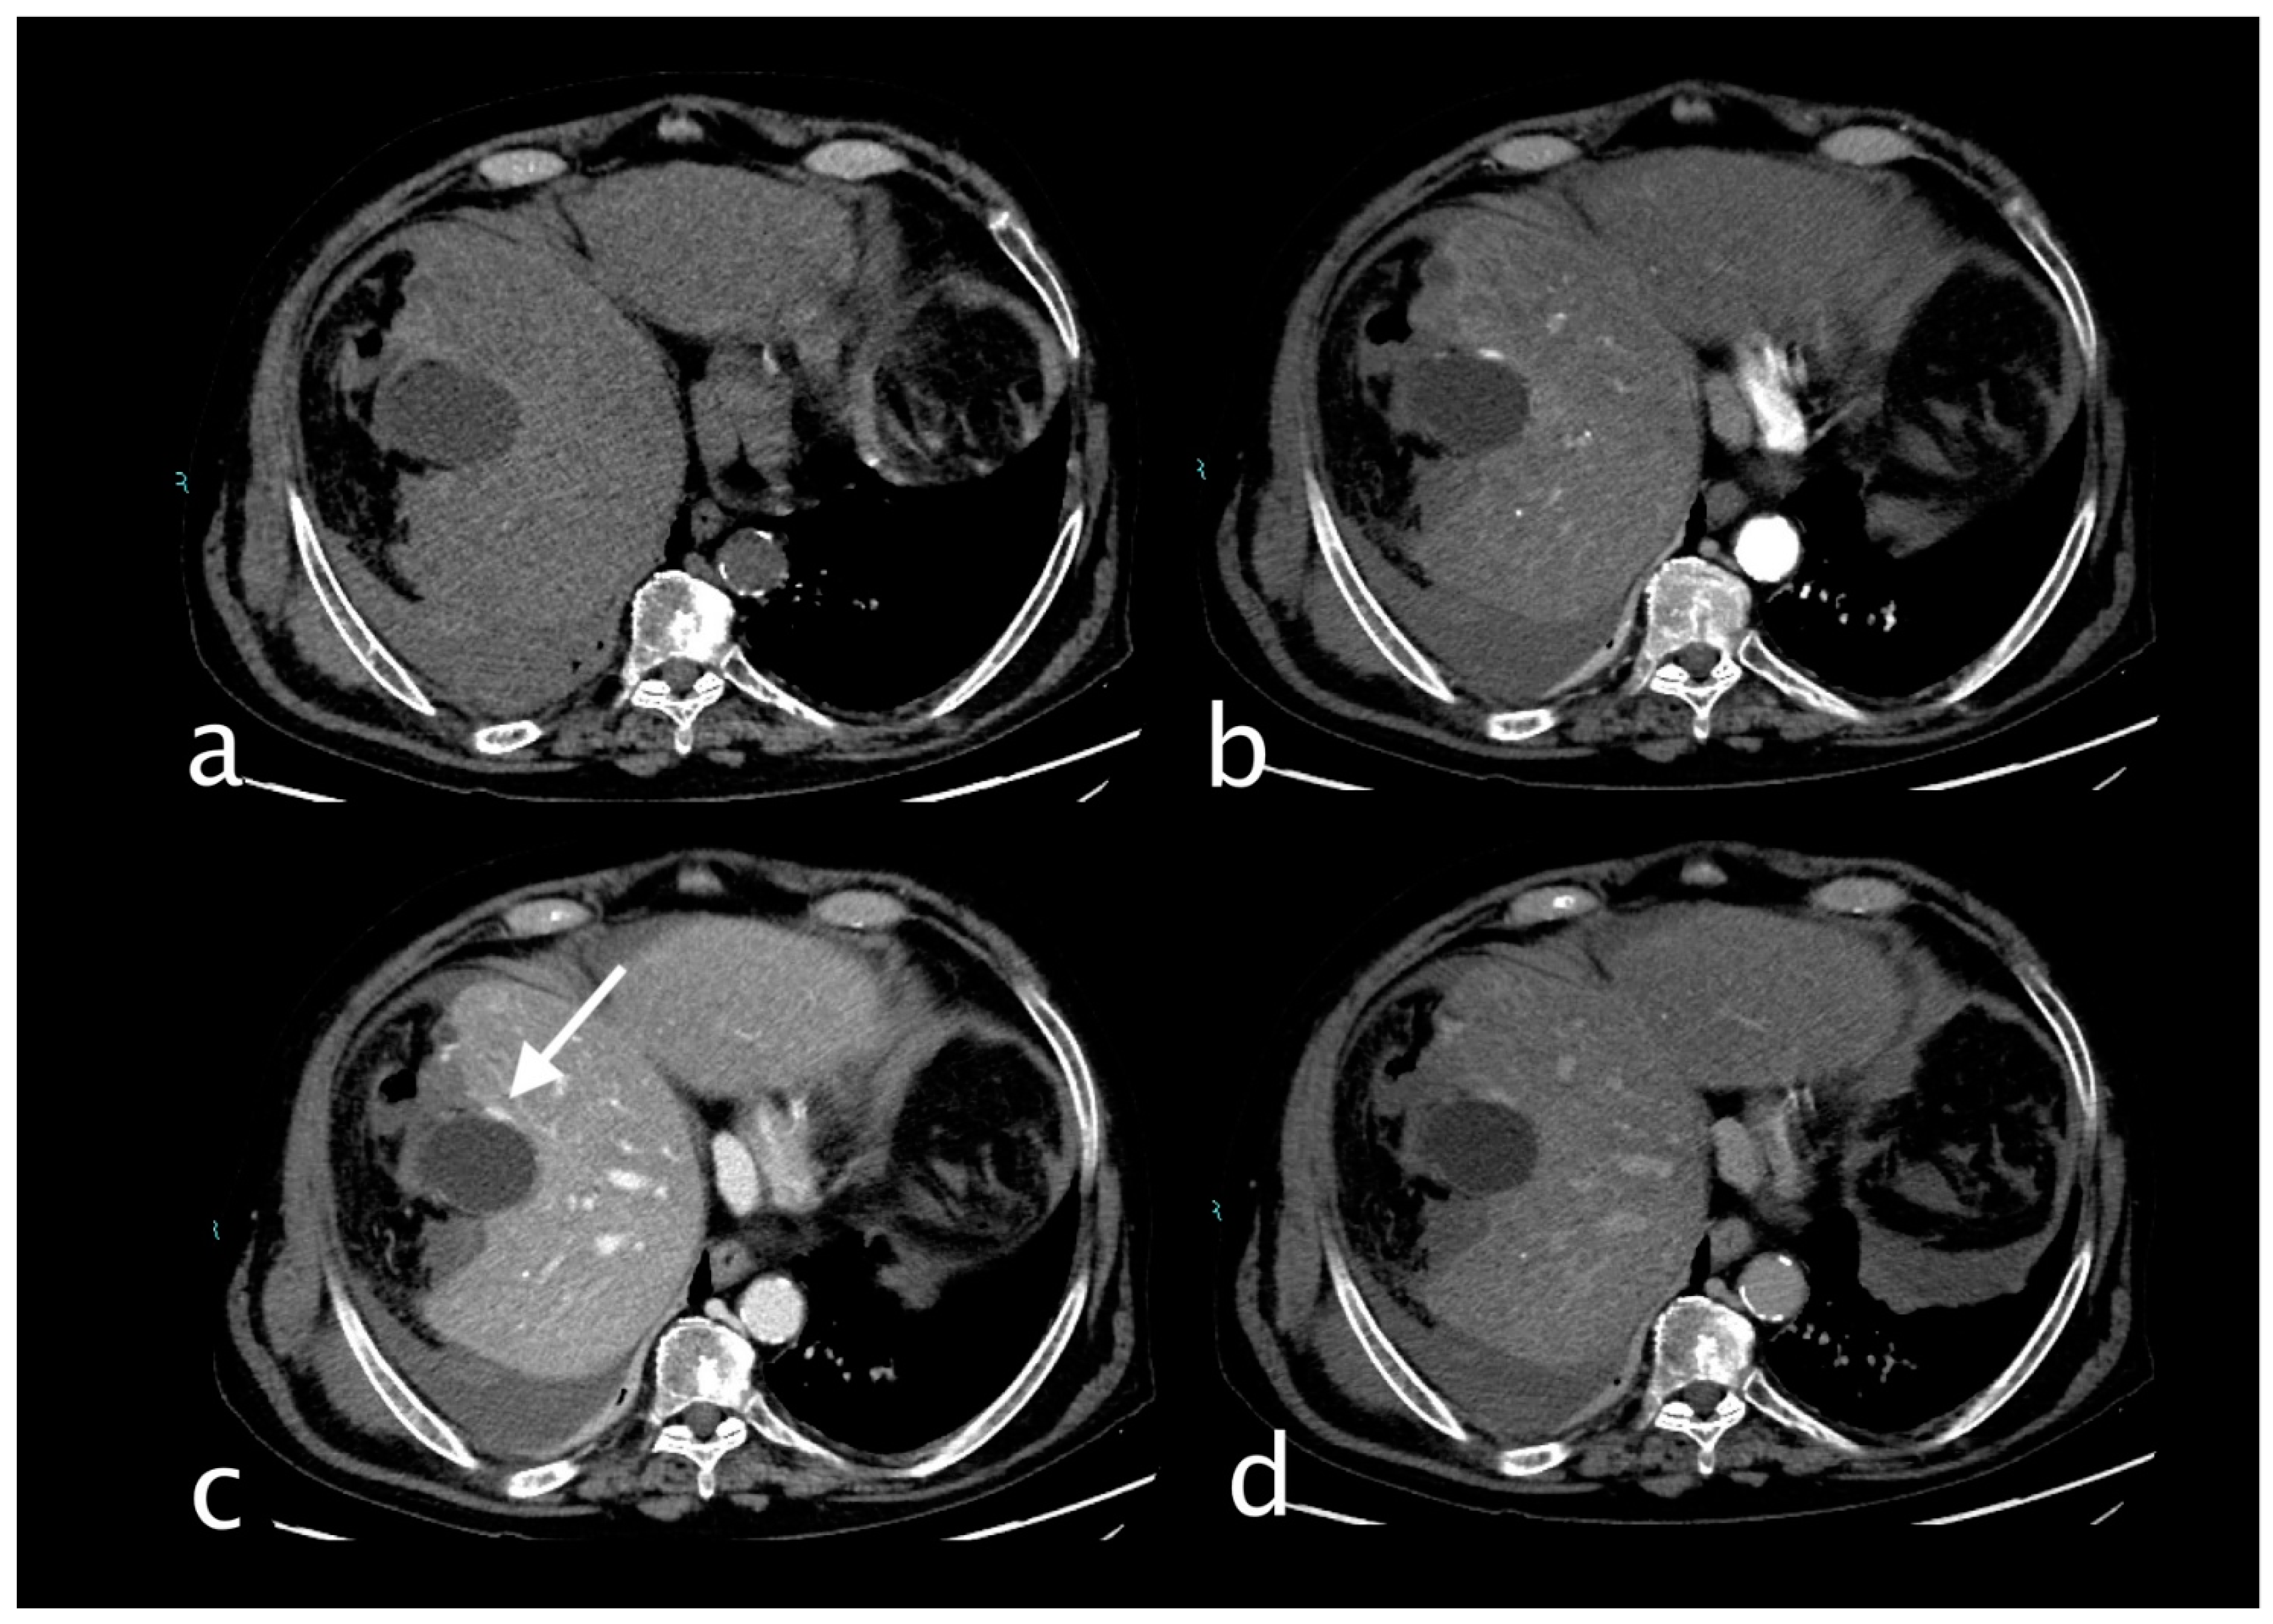

2. Imaging